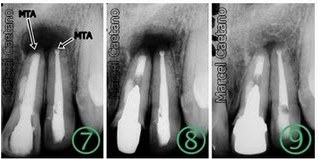

Muitas vezes são realizadas retrobturações, ou seja, tampa-se o ápice dental com um material especial a fim de promover um melhor selamento no fim do canal.Se diagnosticado cedo, o tratamento é rápido e com poucas sequelas.

Paciente apresentou-se com lesão periapical veja RX inicial, foi indicada a cirurgia e no ato foi retirado material para exame histopatologico, para se descobrir a natureza da lesão.

Após com redução da perda óssea

Exame Histopatologico:

Resultado Cisto Odontogênico Inflamatório, Negativo para malignidade.